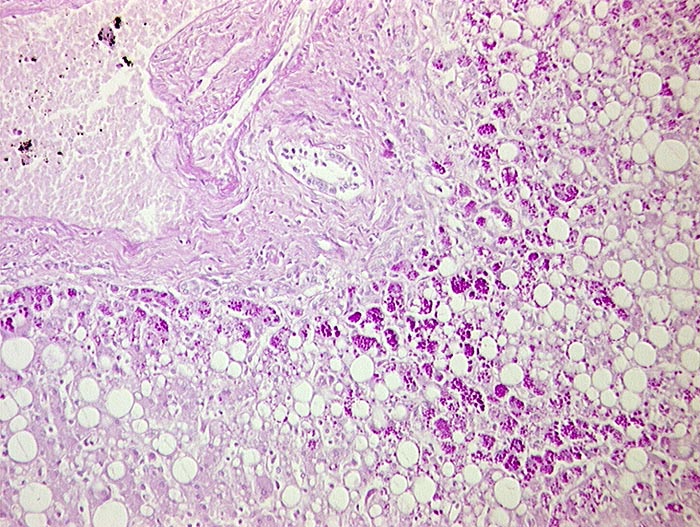

Leber bei Alpha-1-Antitrypsinmangel

Befund

Pathologischer Befund